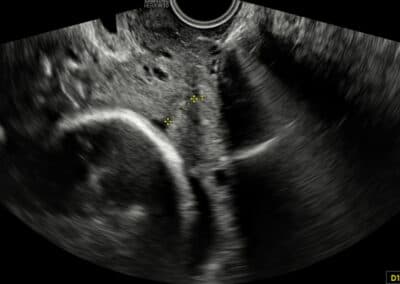

Vyšetření délky kanálu děložního hrdla – normální nález

UZ vyšetření délky děložního čípku dle FMF protokolu

Podmínky FMF certifikace pro vyšetření délky děložního hrdla (cervikometrii):

On-line teoretický kurz (e-teaching) o vyšetření děložního hrdla na www.fetalmedicine.com (část Fetal Medicine Foundation- volba Training & Certification v menu na horní liště, následně položka Certificates of competence – volba modré položky Cervical assessment) Zaslání logbooku dvou snímků a sice normálního a krátkého (méně než 20mm) děložního hrdla